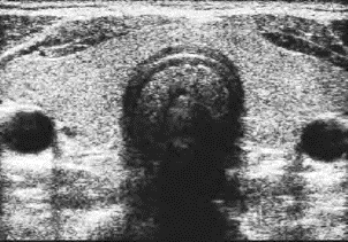

1.横切面(图7-3) 在颈前部横切面上,甲状腺位于颈前及颈侧部的皮肤及肌肉层后方。左、右各一侧叶,中央的峡部将左右叶相连。甲状腺边界十分清楚,包膜呈纤细的较强回声光带,内部为密集中等光点回声,分布均匀。两侧叶此断面轮廓接近三角形,内侧缘略呈弧形。其外后方颈总动脉为圆形管道结构,颈内静脉在颈总动脉前方偏外,呈较扁的薄壁管道结构。峡部较薄,其后方气管显示为声影。在此切面上可测量甲状腺两个侧叶的前后径、横径及峡部的厚度。

图7-3 正常甲状腺超声图像(横断面)